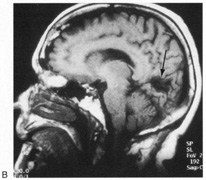

HEMIACHROMATOPSIA.

Achromatopsia in the contralateral hemifield alone can follow unilateral right or left occipital lesions (Fig. 18). Patients are typically asymptomatic until the defect is demonstrated on examination.234,235 Hemiachromatopsia is usually associated with a superior quadrantanopia;234,235,241 therefore, the color defect is only demonstrable in the remaining inferior quadrant. The preserved color vision in the ipsilateral hemifield allows normal or near-normal performance on centrally viewed tests of color vision such as pseudoisochromatic plates. The incidence of hemiachromatopsia is probably underestimated, given its asymptomatic nature and the failure of routine clinical color tests to detect its presence.

Fig. 18. Magnetic resonance imaging scan of patient with stroke causing a right hemiachromatopsia as well as partial superior quadrantanopia.